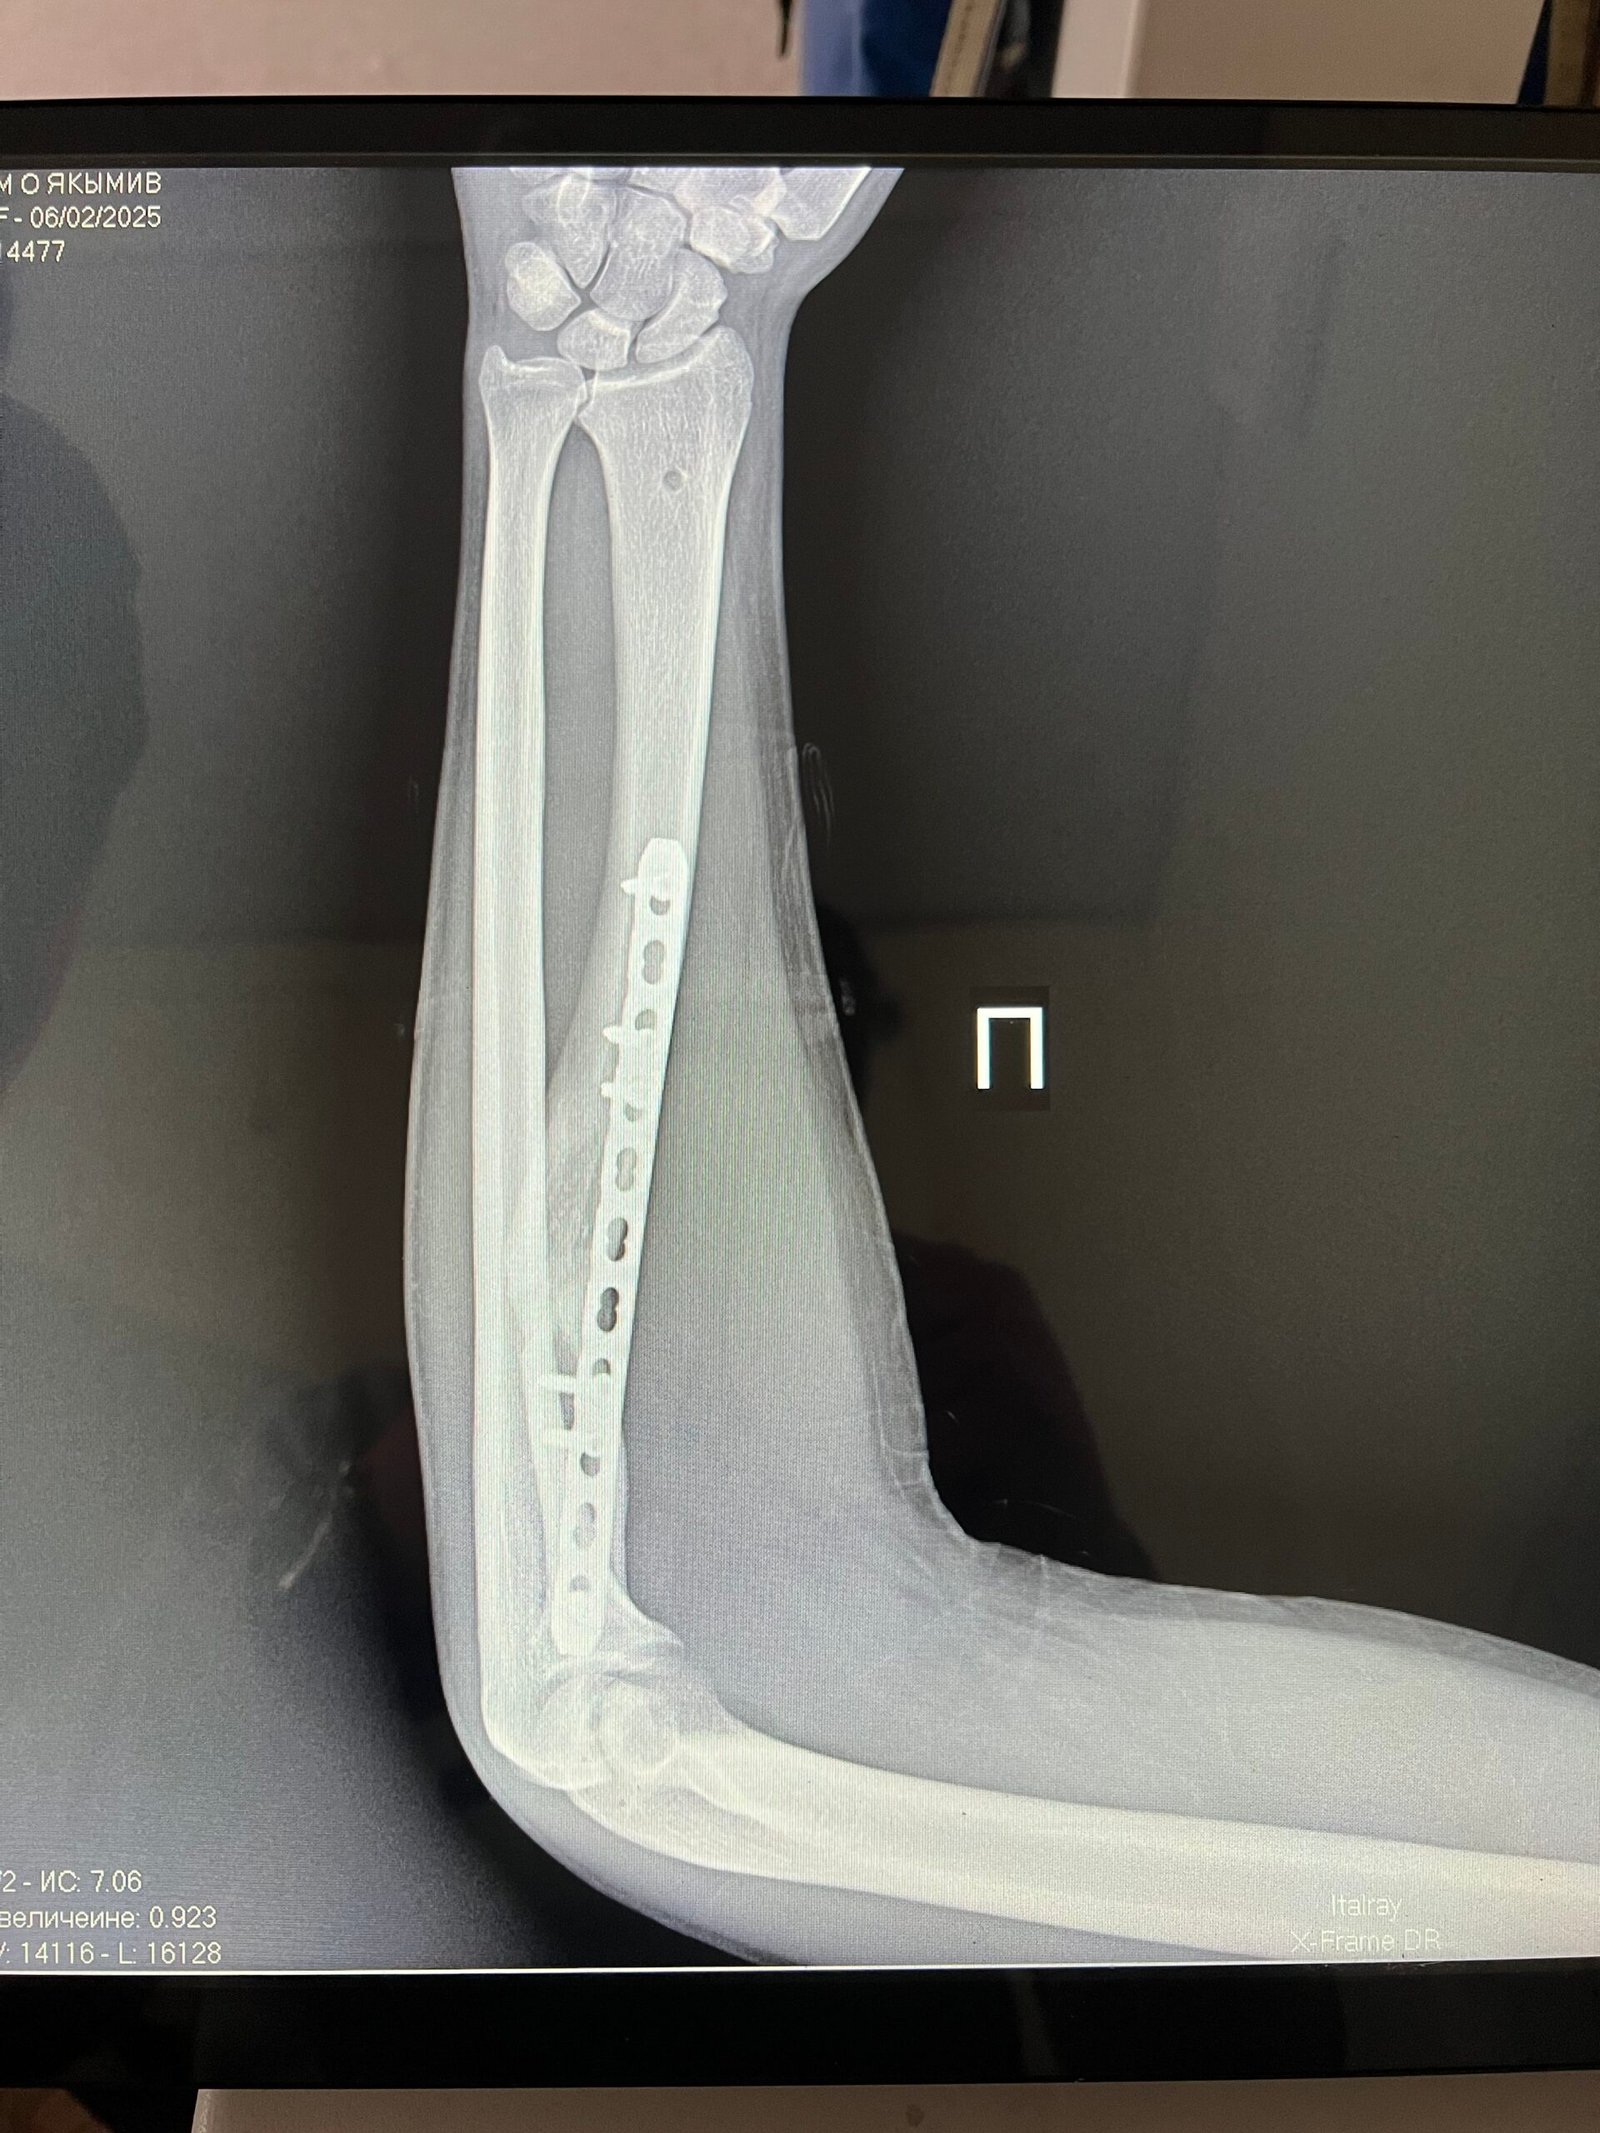

Наслідки важкого поранення обмежили функції руки, та час вимагає ставати в стрій і міцно тримати зброю. Та й правиця у коваля повинна бути міцною і вправною. Після мого повторного звернення Мирослав Ігорович, відгукнувся, спланував і успішно провів кісткову аутопластику дефекту 1 п’ястної кістки МОС пластиною та теноліз розгиначів 1 пальця.

Міцність і функції правиці відновлено. Після реабілітації завдяки якісному лікуванню я знову зможу міцно тримати в руках і використовувати протитанкову зброю, та після нашої спільної Перемоги повернутися до свого ремесла.